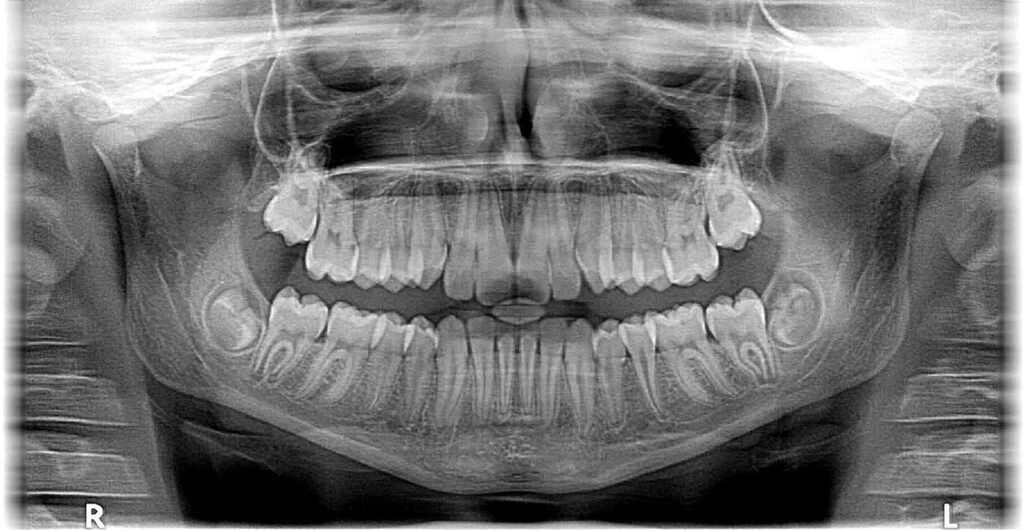

親知らず抜歯

当院では、大学病院でしか抜けないと言われた親知らずも、精密な診査・診断をした上で、基本的に抜くことが出来ます。また、時間のない患者様のために、即日抜歯・複数本の抜歯にも対応していますので、1回で済ませたい方は是非ご相談ください。